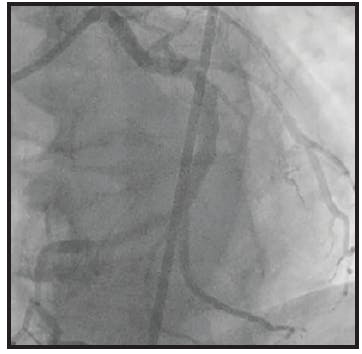

Initial angiography revealed an occlusion of the distal RCA. Mechanical coronary aspiration was performed frontline with CAT RX and Penumbra ENGINE to remove the high thrombus burden. After one pass with CAT RX, the high thrombus burden was removed, resulting in TIMI 3 flow.

With reperfusion to the distal vasculature and clear visualization of the underlying stenosis, a 3.5-mm stent was placed. After IVUS, the stent was dilated to 3.75 mm. Final angiography was performed, showing complete resolution of the underlying lesion (Figure 2).